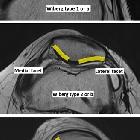

Wiberg classification is a system used to describe the shape of the patella based mainly on the asymmetry between the patellar medial and lateral facets on axial views of the patella. Increasing number type indicates a larger degree of asymmetry.

Classification

- Wiberg type 1 or a

- roughly symmetrical facets

- concave facets

- equally sized facets

- although presumably the ideal shape of the patella, it is in fact rather uncommon, occurring in only 10% of the general population

- Wiberg type 2 or b

- slightly smaller size of the medial facet

- concave aspect of the lateral facet

- Wiberg type 3 or c

- markedly smaller size of the medial facet

- more vertical orientation of the medial facet